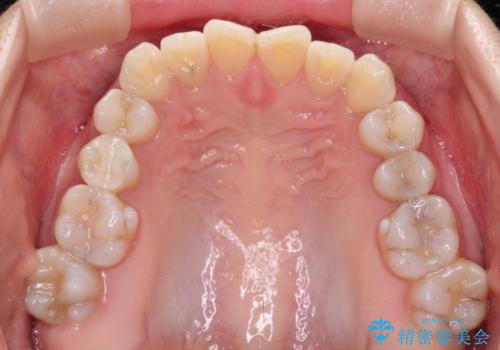

【インビザライン 】前歯の凸凹をなおしたい

- 前歯の凸凹を主訴に来院されました。

インビザライン にて治療を行い、歯並びが綺麗になったと満足していただきました。

前歯のガタガタの量が多かったため、IPR(歯のサイズを小さくするための処置)を行なって治療しました。